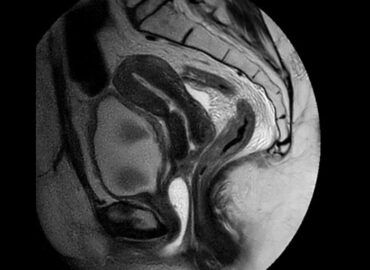

Sexo femenino de 35 años APP Ca de cuello